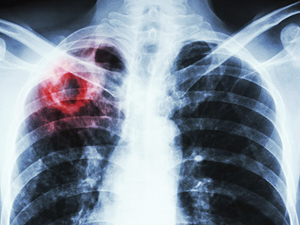

Боротьба з туберкульозом в Україні: можливості ПМГ та нові моделі взаємодії